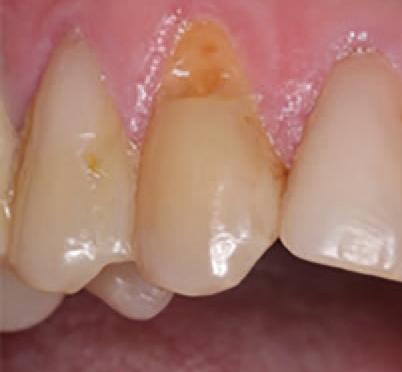

Conservative Management of Class V Lesions: A Case Study Using Advanced Adhesive and High-Performance Flowable Composite

Patient Information

A 72-year-old male presented with a history of restoration loss and recurring sensitivity on tooth #6. The Patient reported that the previous restoration had dislodged, and he now experienced sensitivity localized to the cervical area. His medical history is non-contributory.

Diagnosis and Treatment Plan

Clinical examination confirmed the presence of a small lesion and sensitivity, likely due to exposed dentin.

Treatment Protocol: Caries Detection and Preparation

To improve isolation and soft tissue access, a retraction cord was placed before initiating the procedure (Fig. 2). The tooth was evaluated using a caries indicator dye (Kuraray Noritake Dental), helping to identify any remaining infected tissue beneath the dislodged composite (Fig. 3). Decay removal was completed with a diamond bur, and the enamel was bevelled using a starburst pattern to enhance aesthetic blending (Fig. 4). This preparation design was chosen for visual integration rather than bond strength enhancement.

Figure 1. Initial presentation of tooth #6 showing the Class V lesion with dislodged previous restoration and exposed dentin.

2. Placement of retraction cord to improve isolation and access to the cervical area prior to preparation.

Application of caries indicator dye to identify remaining infected tissue beneath the dislodged composite.